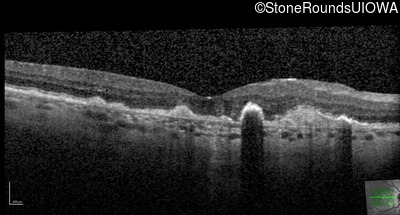

This 43 year old woman has experienced a gradual reduction in her central vision for the past 3 years.

| Malattia Leventinese | EFEMP1 | Arg345Trp CGG>TGG | AD |